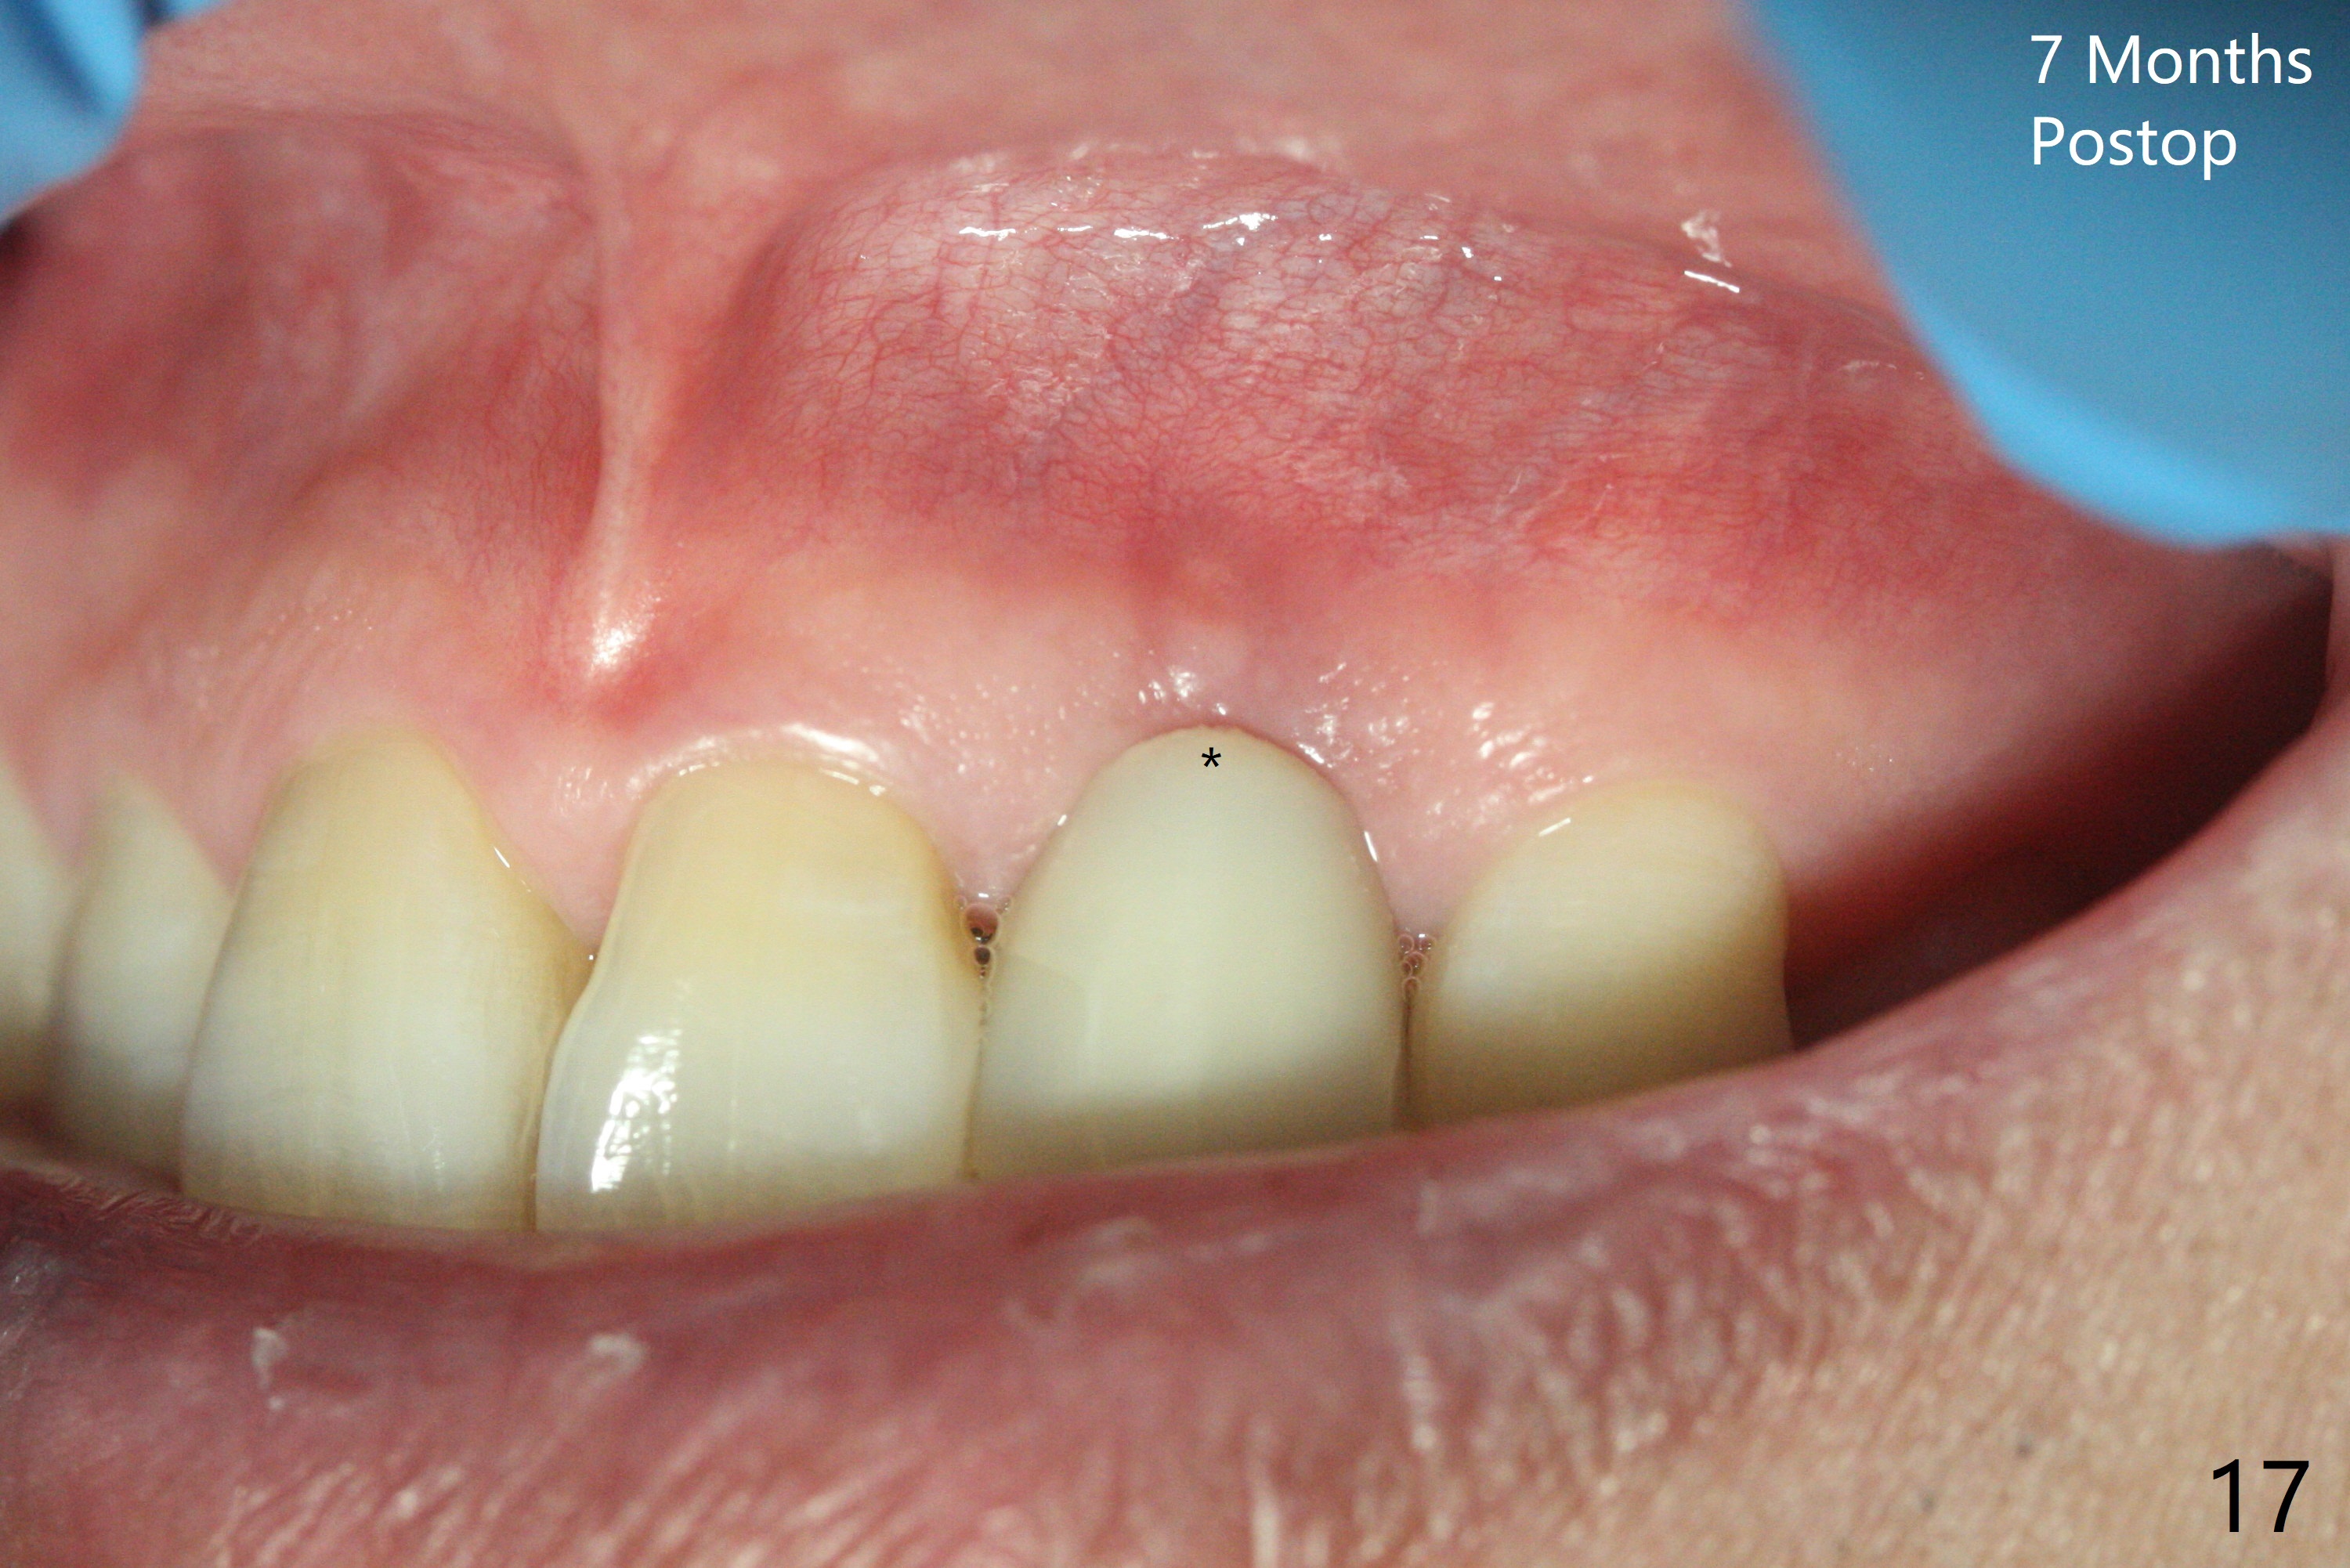

病人回来带来瘘道(图一),不过不会增加难度,病牙去除,它便自动消失。尽管颊侧骨壁完全失去,颊侧牙龈仍丰满(图二),为什么呢?第一,因为粗大牙根存在,第二两旁牙齿,牙槽骨撑着帐篷(侧切牙颊侧牙龈),第三,牙冠。为了防止术后牙龈塌陷,尽量不切开,即刻放置植体(牙根);由于前牙缘故,这次植体不能很大,所以植骨必须过度(over grafting),最后即刻制作临时牙冠,撑住牙龈。这就是所谓每个人进入角色。这个牙根有一种先天性畸形:dens in dent (图三(腭侧观):箭头)。尽管腭侧牙根畸形,腭侧骨壁吸收临床上并不严重,所以钻洞仍偏腭侧。当预定最后钻头还在钻洞时,填入大量粘性骨块(图四:*),细长植体还没有完全卡入鼻底(图五),最后好像可以(图六,七)。植体,骨粉入位(图八),最后临时牙冠出场(图九)。尽管植体小,术后一周临时牙冠仍然可以维持牙龈原有形状(emergency profile,图十:箭头(*:树脂强化牙冠固定))。图十一以不同角度显示瘘道缩小。术后三周取出有些松动的临时牙冠,骨粉虽然还没有被肉芽组织整合,但是显得正常,周围牙龈健康(图十二)。术后4个月牙龈形态正常(图十三),没有触痛;颊侧骨板轻度凹陷(图十四);骨粉仍在原位(图十五)。术后7个月骨粉仍在原位(图十五,十六,但是冠部密度减低(可能骨粉流失,需要牙周或者树脂敷料保护)),没有螺纹暴露。但是牙冠边缘暴露,说明牙龈收缩(图十七,与图十三对比),颊侧骨板仍塌陷(图十八)。插入龈线取得多个目的:修整基台边缘,取模,颊侧牙龈推向颊侧,有利于即将衬里牙冠龈缘进入龈下(图十九)。取模后牙冠边缘(图二十:<)衬里,然后修整,变窄,以便插入龈下,促进颊侧牙龈下降(图二十一,二十二)。术后8个月牙冠粘固前牙龈健康(图二十七,八),牙冠(图二十九)固位后,病人满意(图三十),咬合调整(图三十一),注意腭侧粘固粉流出通道(<)。